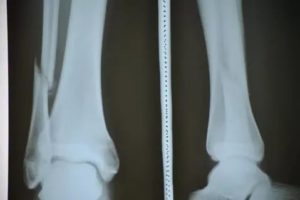

Приводим фото открытого перелома костей голени.

При травме большой берцовой кости

Перелом наружного мыщелка большеберцовой кости часто имеет открытый характер, потому что кость расположена ближе к кожным покровам. В случае закрытого перелома доктор с легкостью может нащупать сломанные кости во время осмотра. Если повреждаются связки, то происходит перелом большой берцовой кости со смещением. О этом может свидетельствовать укорочение поврежденной конечности.

После получения травмы происходит искривление ноги, от повреждения сосудов появляется явно выраженный кровоподтек, место травмы начинает отекать, становится невозможно наступить на больную конечность.

Если повреждаются обе кости одновременно, то симптоматика будет такая же, как при переломе тибиального участка большой берцовой кости.

Если человек упал на прямые ноги, то часто возникает перелом мыщелка большеберцовой кости, которых в голени два. Такие травмы бывают вдавленными, когда один отломок на несколько сантиметров входит в другой отломок.